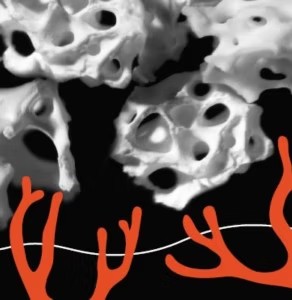

Po 3~5 dniach

W ciągu 3 do 5 dni naczynia krwionośne aktywnie zbliżają się do miejsca przeszczepu.